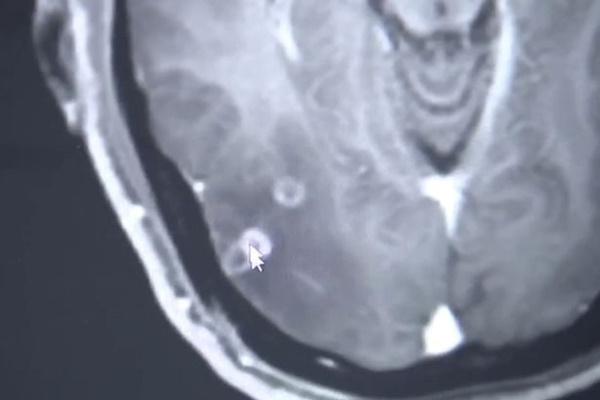

Chia sẻ trên trang Pear, bác sĩ Vương nói rằng: "Có nhiều sự tổn thương trong não của bệnh nhân. Sán dây cũng có ở trong phổi và lấp đầy các cơ bên trong khoang ngực của ông ấy và gây tổn hại đến các cơ quan".

Bác sĩ Vương nói rằng sán dây đã gây tổn thương đến các cơ quan trong cơ thể bệnh nhân.

Cuối cùng, bác sĩ cũng tìm ra nguyên nhân là do anh ta có một loại kí sinh trùng hiếm gặp trong não. Anh được chẩn đoán mắc bệnh sparganosis, một bệnh nhiễm trùng gây ra bởi một loại ấu trùng sán dây được gọi là Spirometra. Điều đáng nói, các bác sĩ cho rằng con sán dây dài khoảng 12cm này đã kí sinh trong não của anh tới cả 10 năm mà không biết.

Phải mất 2 giờ phẫu thuật các bác sĩ mới loại bỏ hết sán dây khỏi não của người đàn ông. "Cuộc phẫu thuật rất mạo hiểm. Sán dây sống đang di chuyển trong não của bệnh nhân và chúng tôi phải loại bỏ tất cả, nếu không phần còn sót lại có thể lại sinh sôi", bác sĩ Gu Youming, bác sĩ phẫu thuật cho bệnh nhân chia sẻ với AsiaWire.